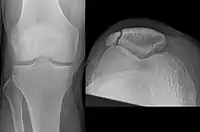

Types

The patella can break in various ways depending on the way it is injured, and into two or more pieces.[1] Types include transverse, the most common, with one fracture line;[5] marginal; osteochondral; and the rare vertical type, or stellate, where a direct compression force gives rise to a comminuted pattern.[5][7] Patella fractures can be further classified as displaced, where the broken ends of bone do not line up correctly and separate by more than 2mm, or undisplaced and stable where pieces of bone remain in contact with each other.[1][7] If fragments of patella bone stick out from the skin it is known as an open patella fracture, and closed if the overlying skin is intact.[1]